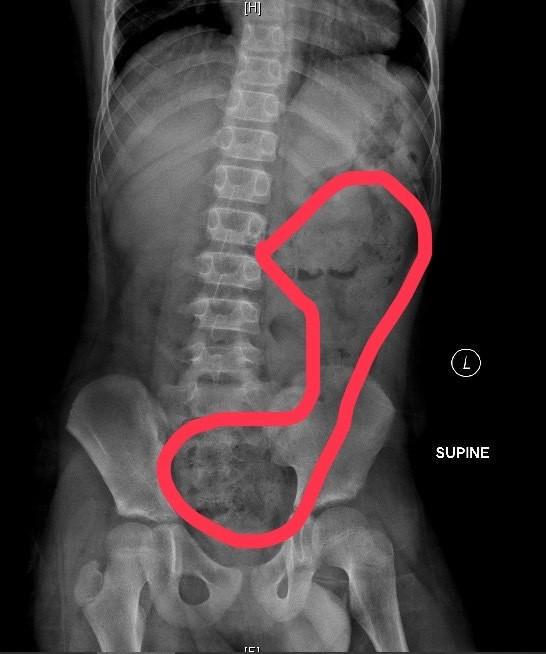

阮綜合醫院另也收治一名6歲女童,她的肚子痛得直哭叫,腹部明顯異常脹大,經腹部X光檢查發現她"一肚子大便"!原來剛上小學,可能還未習慣上下課時間,憋便到連幾天沒上大號,也記不清楚,直到嚴重腹痛才送急診。

阮綜合急診兒科主治醫師蕭宇超表示,2童都屬小兒「功能性便秘」,即排除生理結構與疾病問題,因排便、飲食習慣或心理因素所造成的便秘,當孩童一個月內,每周排便少於3次,腹脹且解便時疼痛、糞便過硬或過粗,就是便秘了。